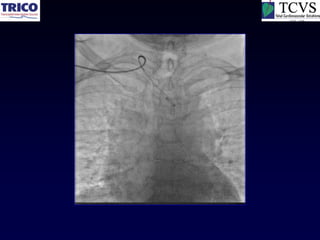

Extensive anterior wall MI-1 hour

Acute IWMI &

Cardiogenic Shock